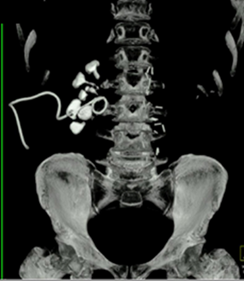

Vad ses på bilden?

A

Samlingssystemet med uttalad hydronefros, uttalad hydrouretär ned till konkrement i övergång mellan proximal uretär och mellersta delen ureätär

DT visar

• Samlingssystemet med uttalad hydronefros, uttalad hydrouretär ned till konkrement i övergång mellan proximal uretär och mellersta delen ureätär